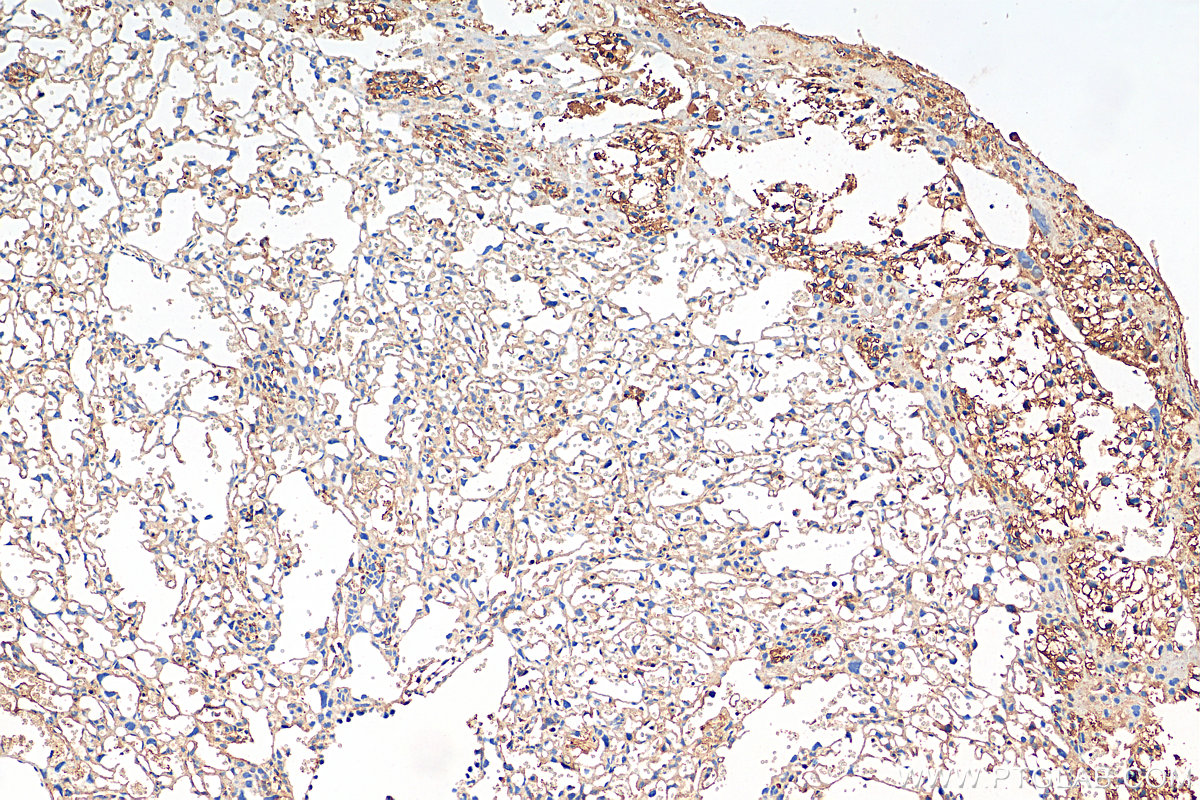

| Positive IHC detected in | mouse lung tissue, mouse placenta tissue Note: suggested antigen retrieval with TE buffer pH 9.0; (*) Alternatively, antigen retrieval may be performed with citrate buffer pH 6.0 |

| Immunohistochemistry (IHC) | IHC : 1:50-1:500 |

EDN1, also named as Endothelin-1, PPET1 and ET-1, belongs to the endothelin/sarafotoxin family. Endothelins are endothelium-derived vasoconstrictor peptides. Emerging basic science, and animal and human data all suggest that EDN1 is a potentially important contributor in the pathobiology of fibrosing disorders, including those that affect the lung(PMID:20055532 ).